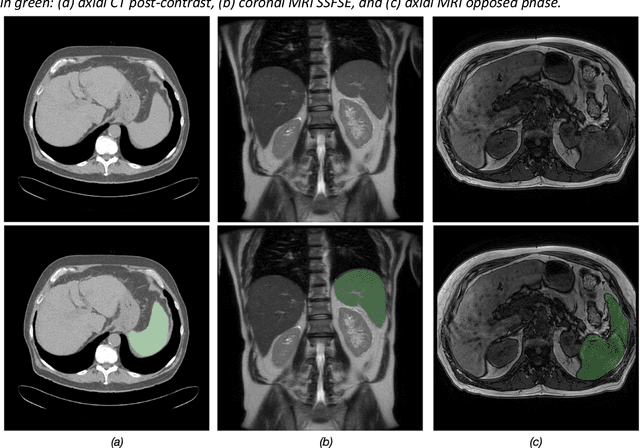

Abstract:Spleen volumetry is primarily associated with patients suffering from chronic liver disease and portal hypertension, as they often have spleens with abnormal shapes and sizes. However, manually segmenting the spleen to obtain its volume is a time-consuming process. Deep learning algorithms have proven to be effective in automating spleen segmentation, but a suitable dataset is necessary for training such algorithms. To our knowledge, the few publicly available datasets for spleen segmentation lack confounding features such as ascites and abdominal varices. To address this issue, the Duke Spleen Data Set (DSDS) has been developed, which includes 109 CT and MRI volumes from patients with chronic liver disease and portal hypertension. The dataset includes a diverse range of image types, vendors, planes, and contrasts, as well as varying spleen shapes and sizes due to underlying disease states. The DSDS aims to facilitate the creation of robust spleen segmentation models that can take into account these variations and confounding factors.